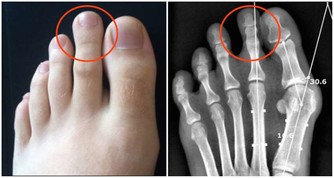

8. 你的呼吸急促

硒蛋白的另一個重要的工作是保護你的心臟,有人甚至因為缺硒導致心臟衰竭。